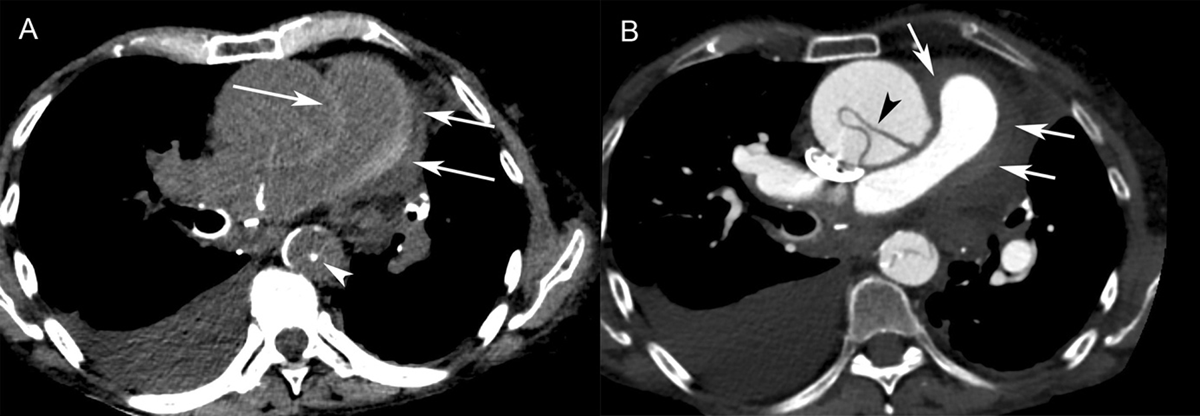

Figure 1

Patient 1. (A) Axial non-contrast-enhanced CT showed circumferential high attenuation along the walls of the pulmonary trunk (70 HU) and right pulmonary artery (arrows), consistent with an intramural hematoma. An ascending aortic aneurysm with displacement of atherosclerotic calcifications into the lumen of the descending aorta (arrowhead) was seen. Right pleural effusion was also visible. (B) Contrast-enhanced CT revealed Stanford type A aortic dissection. The intimal flap was seen in the ascending aorta (arrowhead) and descending aorta. The high attenuation area of the pulmonary arterial wall was non-contrast-enhancing (arrows), which was consistent with pulmonary artery intramural hematoma.